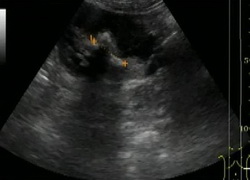

Рис. Ультразвуковое исследование.